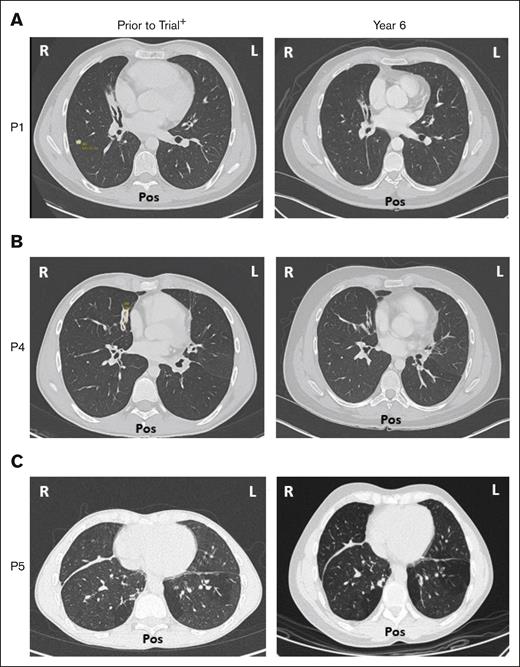

Five of 6 patients had a history of respiratory disorders. Half had bronchiectasis before receiving leniolisib; none progressed and all are stable at year 6 (Figure 7). Pulmonary function tests in 5 of 6 patients revealed no new or worsening conditions through year 6.

Bronchiectasis throughout treatment with leniolisib. Lung computed tomography scans from (A) P1, (B) P4, and (C) P5 who developed bronchiectasis before entry into the trial (left) and year 6 of treatment with leniolisib (right). L, left; Pos, posterior; R, right. +Images for P1 and P4 were taken ∼1 year before entry into the DFT, and the image for P5 was taken ∼4 years before exposure to leniolisib.

Regarding lung disease, bronchiectasis in all 3 affected patients showed no progression. More than half of the cytopenias that were present during treatment across the trials resolved by year 6. Patients whose cytopenias did not fall WNLs improved; notably P2 had a marked increase of platelets from 53 × 109/L to 148 × 109/L by year 6.